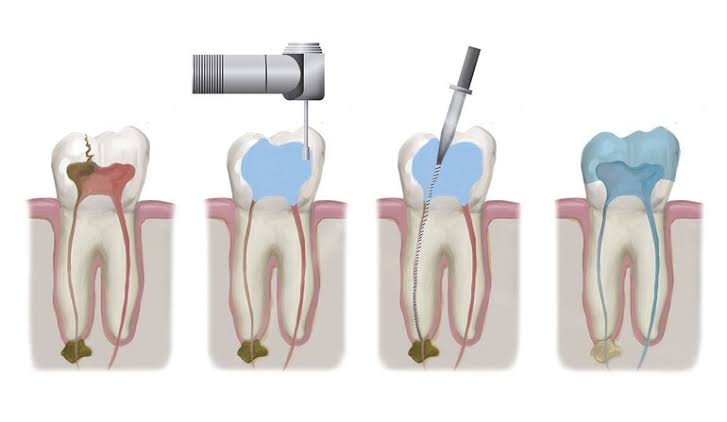

How is a root canal procedure performed?

The root canal procedure typically involves the following steps:

Root Canal Treatment

Root canal treatment is a procedure done when the tooth decay reaches the pulp causing pain & inflammation.

The procedure is

- Removal of infected tooth structure

- Clearing & Disinfection

- Filling with an inert material

- Restoration with crown or cap